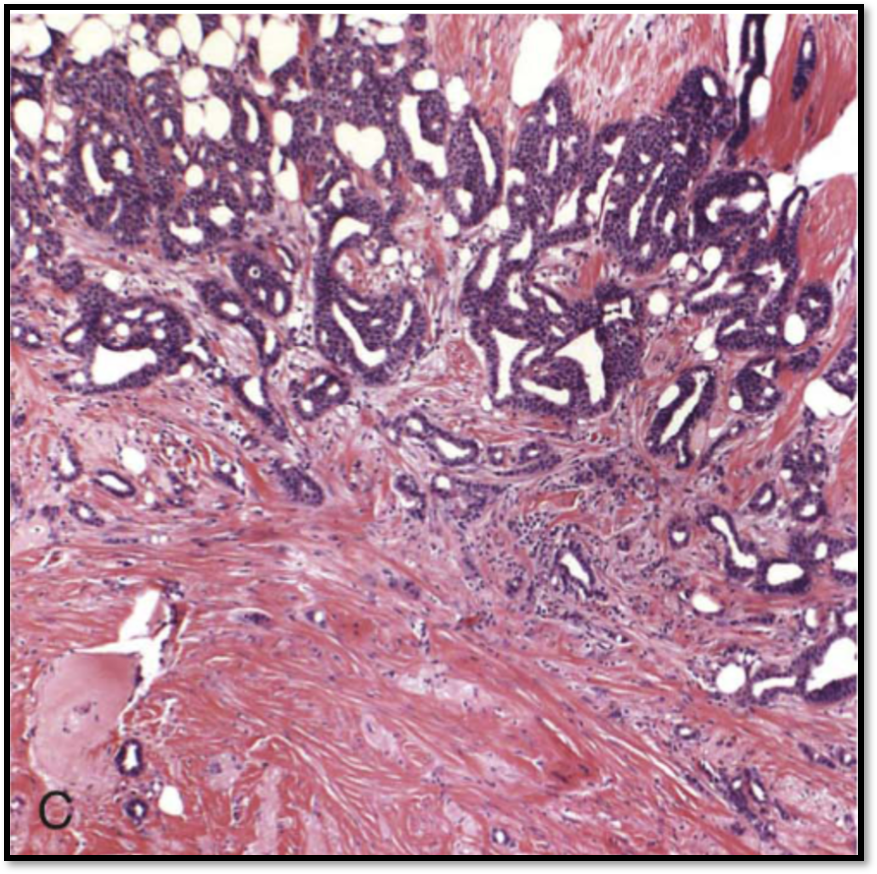

Microscopy: See attached image

Fibroadenoma

Gross: well-circumscribed, rubbery, grayish white nodules that bulge, slitlike spaces